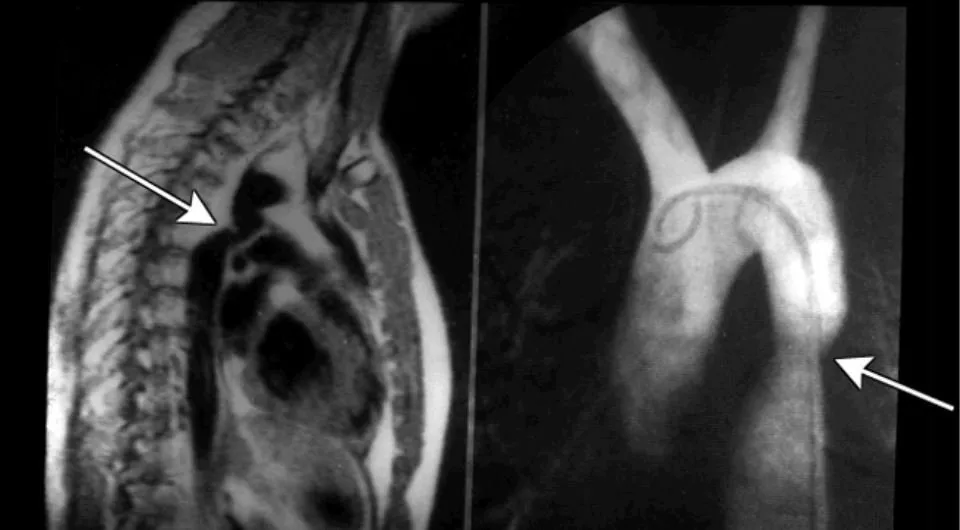

• Chụp cắt lớp vi tính động mạch chủ: Là phương tiện quyết định chẩn đoán hẹp eo động mạch chủ ở người lớn. Trên phim chụp xác định được vị trí, hình thái chỗ hẹp, các tuần hoàn bàng hệ và các tổn thương phối hợp.

• Thông tim chẩn đoán: Đưa các dụng cụ qua đường mạch máu ngoại biên (động mạch đùi hoặc động mạch quay) để chụp chỗ hẹp và tuần hoàn bàng hệ. Hẹp eo động mạch chủ được chẩn đoán khi chênh áp trên 10mmHg giữa động mạch chủ lên và động mạch chủ xuống. Tuy nhiên chênh áp không phản ánh mức độ hẹp vì có thể ảnh hưởng bởi các tuần hoàn bàng hệ.

Chẩn đoán hẹp eo động mạch chủ dựa trên X-quang.